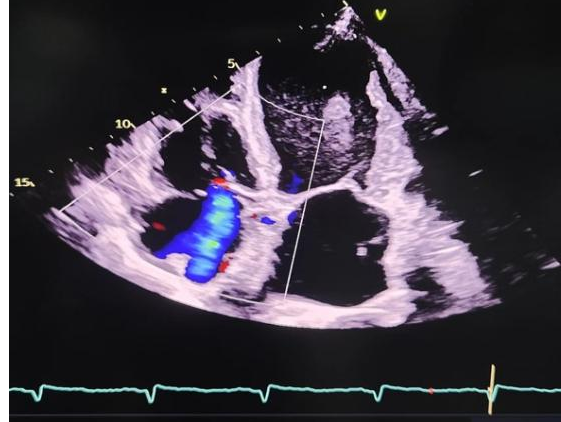

术后超声